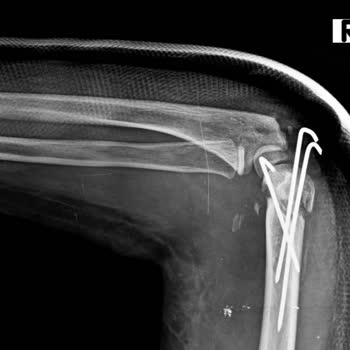

Zeytinburnu'daki Koç Üniversitesi acil bölümüne 03.10.2024 tarihinde kızım z. D**. Ş. Sol ayak bileğinde bileğinde şiddetli ağrıyla acil bölümüne götürdüm. Acilde röntgen çekildi. Sol ayağında olmasına rağmen 2 ayağını da röntgen çekilmiş olduğunu gördük. Acil de ayağında kırık olmadığı ortopedi dok...